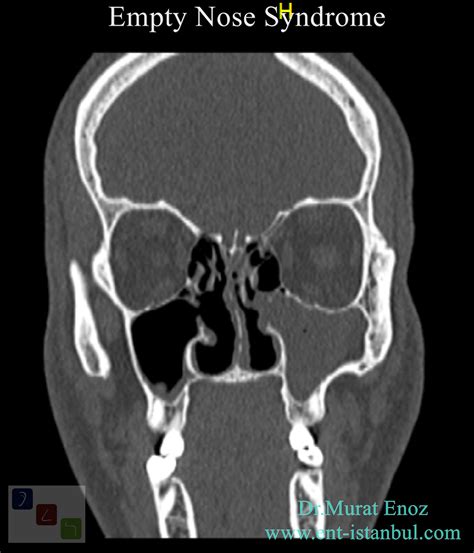

• Imaging Studies: CT scans or MRI can provide detailed images of the nasal structures and help identify any abnormalities.